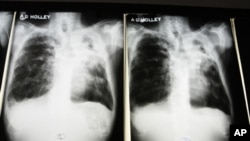

Tuberculose mata em Malanje

Pelo menos oito pacientes infectados com bacilo de Koch perderam a vida durante os primeiros três meses deste ano, anunciou nesta cidade o director geral do Hospital Sanatório de Malanje Manuel Adelino do Nascimento.

Nascimento disse que houve um total de 91 pacientes com essa doença acrescentando que “o estado em que muitos se apresentam no nosso hospital é extremamente grave e que muitas as vezes o pessoal pouca coisa tem a fazer”.

Cinco desses doentes “estão associados ao VIH que é uma patologia, que normalmente está sempre associado a tuberculose”.